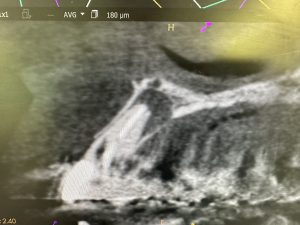

神奈川歯科大学OB長尾論文より

ご覧のとおり、ラルゴでは短く到達しないが

マニーだと余裕で穿通する

エンドバキュームは重宝サクション

長尾先生感謝申し上げます